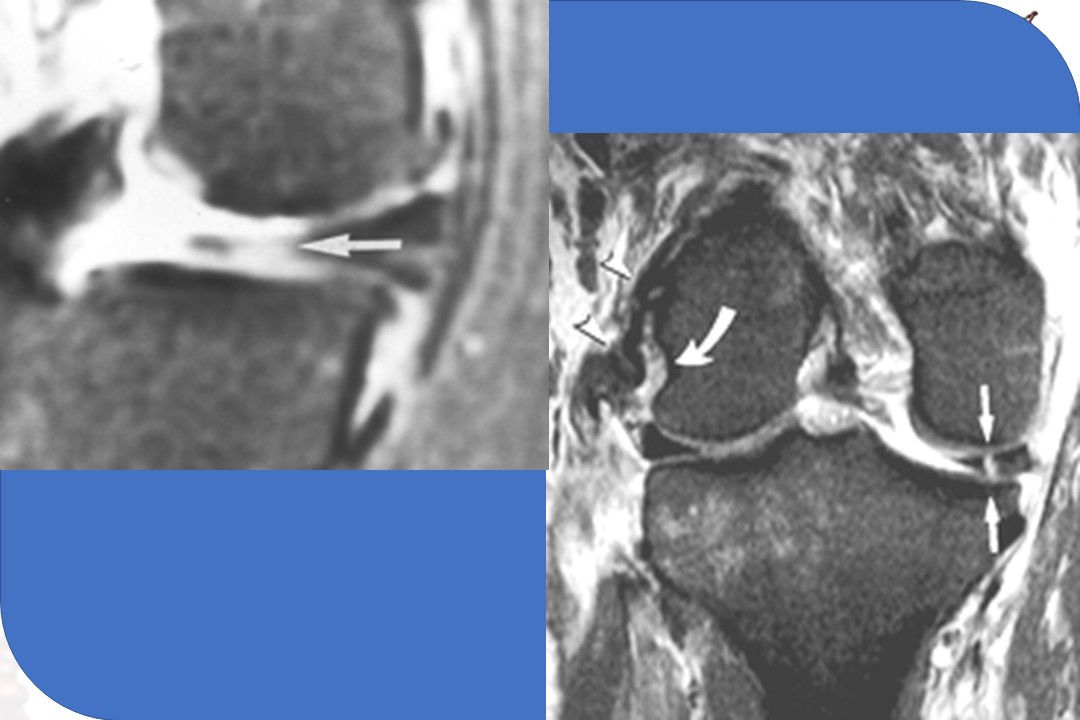

“半月板病变MR诊断PPT” 的相关文章